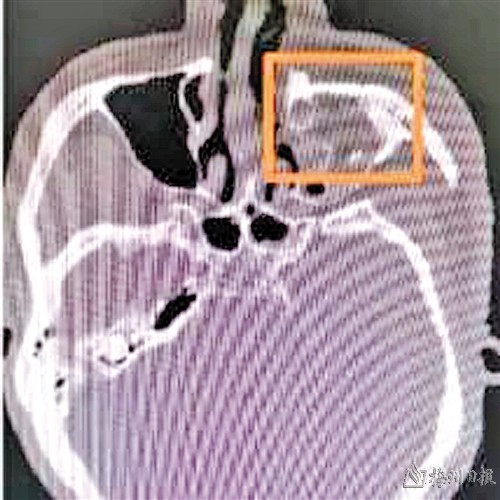

术前颌面骨骨折塌陷

这3年里,丘先生找过多家医院进行“填充”等矫正术,但因骨框架已经畸形,填充结果均不理想。近日丘先生到梅州市人民医院整形外科就诊,整形外科负责人、主任医师石伦刚博士为患者进行了详细的检查,发现患者鼻根部塌陷,鼻根与鼻背呈台阶状,左侧鼻侧壁塌陷,左侧眼眶内侧及面中部凹陷,通过颌面部CT三维重建检查显示患者鼻骨及上颌骨额突和颌面骨骨折。